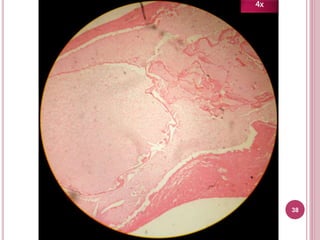

4x